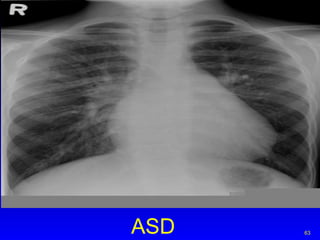

ASD